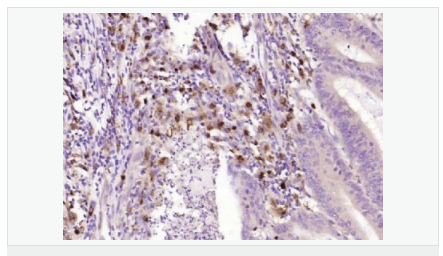

| 产品应用 | WB=1:500-2000 ELISA=1:5000-10000 IHC-P=1:100-500 IHC-F=1:100-500 ICC=1:100-500 IF=1:100-500 (石蜡切片需做抗原修复) not yet tested in other applications. optimal dilutions/concentrations should be determined by the end user. |